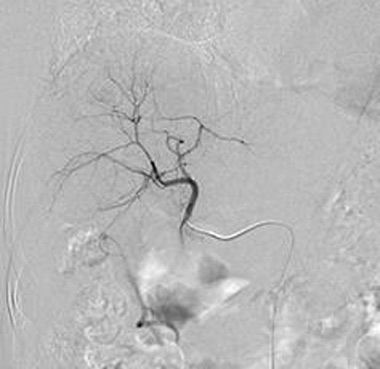

血管造影装置

血管造影装置は、カテーテル

(特別な管)を

血管に挿入して造影剤を流し、

血管の形態を動画や静止画として

描出する装置です。

循環器内科医はその画像を基に、狭くなった血管に対して小さな風船や金属の筒を用いて治療を行います。主に狭心症や心筋梗塞などの虚血性心疾患に対して治療する経皮的冠動脈形成術(PCI)や、末梢血管、腎動脈狭窄・閉塞に対して治療するEVT、不整脈に対して治療するアブレーション等に使用されます。

IVR-CT

Interventional radiology

computed tomography

IVR-CT装置は、1つの部屋に血管造影装置と

CTが装備されており、部屋を移動すること無く治療と

CT撮影を行う事ができるため、

より高度な治療を行うことが可能となっています。

主に放射線科や脳神経外科の血管内治療等に使用しています。放射線科では、肝細胞癌に対して治療するTACEや、外傷等によって体内に生じた出血を止血するTAE、透析患者さんの狭くなったシャント血管を広げるPTA、CTを用いて正確な位置を把握しながら生検するCTガイド下生検などに使用しています。脳神経外科では、脳梗塞に対して治療する血栓回収療法や、脳動脈瘤に対して治療するコイル塞栓術、頚動脈狭窄症に対して治療する頚動脈ステント留置術などに使用しています。